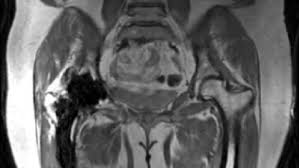

If you are scheduled for prostate mri, please click here. A complete scan, depending on the sequences performed, and need for contrast enhancement may take 1 hour or more. How to prepare for the test: Abdominal mris are used for a variety of reasons, such as examining: How long to wait after mri? What are the risks of an mri of the abdomen? But the magnet is very powerful. However, some specialized pelvis mri exams are only done in the main hospital.

What do i do after my scan? Newer scanners complete the process in less time. But the magnet is very powerful. In some cases, it may take up to about 2 hours. Do you have to drink anything before a mri scan? Most pelvis mri exams are done in the main hospital, acc or placer clinics. The mri of the abdomen will take approximately 60 minutes. How long to wait after mri? Abdominal mris are used for a variety of reasons, such as examining: How will you get the test results? Please contact the doctor who ordered the test for any test results. What are the risks of an mri of the abdomen? How to prepare for the test:

Please contact the doctor who ordered the test for any test results. In some cases, it may take up to about 2 hours. What do i do after my scan? The doctor who ordered the test will receive the results. How long does it take to get mri scan results? Do you have to drink anything before a mri scan? Newer scanners complete the process in less time. What are the risks of an mri of the abdomen? The images of your scan will be examined by a radiologist and the results will be sent to your referring physician who will review the results with you. Abdominal mris are used for a variety of reasons, such as examining: But the magnet is very powerful. How will you get the test results? Most pelvis mri exams are done in the main hospital, acc or placer clinics.